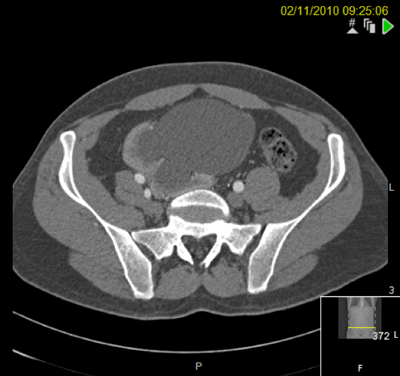

The patient postoperatively.